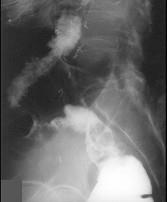

问题 女,50岁,便血10余年,加重1年(连续出血),近2个月大便时肛门常滴鲜血,量较多,X线检查如图,最可能的诊断是 ( )

选项 A.直肠癌 B.直肠绒毛状腺瘤 C.直肠淋巴瘤 D.直肠转移瘤 E.直肠结核

答案 B